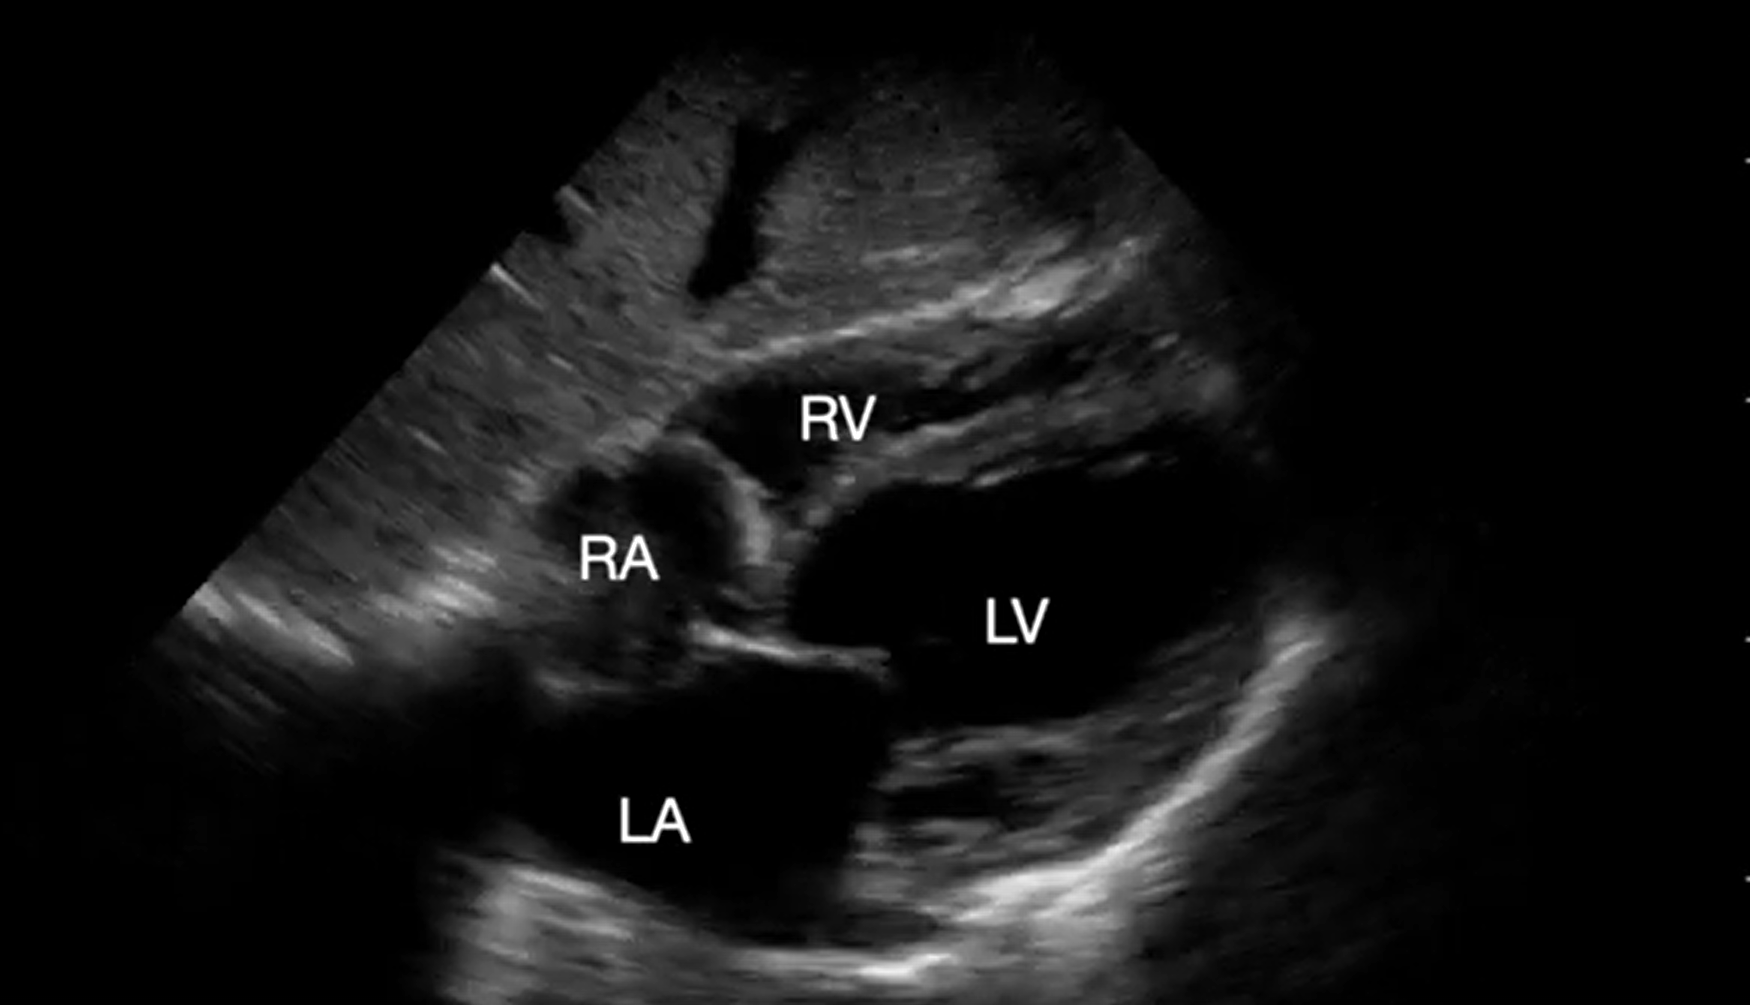

Acute RV failure caused by pulmonary embolism (PE) is a common cause of cardiac arrest in up to 30% of patients with PEA arrest.9 Typical ultrasound findings include RV and RA dilatation on the four-chamber and septal flattening (so called D-sign) on the short-axis views. Also, RV systolic function is reduced in about half of the patients, as evidenced by a decreased tricuspid annular plane systolic excursion on the apical four-chamber view10 (Video 5). If color doppler is applied over the tricuspid valve, significant regurgitation is commonly found. While finding a thrombus in transit in the right heart chambers or within the pulmonary arteries is diagnostic of acute PE, it is rarely visualized and advanced imaging skills are required to locate thrombus.

Supplemental Video 5. Subcostal 4-chaber view demonstrating dilated and depressed right ventricular function. RA, right atrium; LA, left atrium; RV, right ventricle; LV, left ventricle (click to view)

The above findings (other than thrombus-in-transit) are not pathognomonic to PE as they are also seen during a pulmonary hypertensive crisis (PHTC). Chronic changes presenting as RV free-wall hypertrophy (thickness greater than 5 millimeters in diastole) and RA dilatation make a PHTC more likely, whereas a thin-walled RV free wall and a normal size RA point toward an acute process. Finally, chamber sizes should only be assessed in patients with preserved cardiac activity, as the RV can appear dilated in asystole independent of the etiology of cardiac arrest.11 If PE is suspected, the lower extremity venous ultrasound can be performed to evaluate for deep venous thrombosis. Evidence of a thrombus warrants a careful risk/benefit analysis to initiate empiric anticoagulation or thrombolytic therapy.

The responding resident is alerted to an acutely decompensating patient in the SICU or medical or surgical ward by direct call from the primary service or by overhead Code Blue page. On arrival, the resident prepares to serve as a sonographer and complete an EASy-ALS exam. The ultrasound probe is placed in the subcostal window before the pulse/rhythm check without obstructing chest compressions. The code leader, a senior primary care team provider, is responsible for holding and resuming chest compressions. The code leader assigns a nurse to count down 10 seconds during the pulse/rhythm check; this is standard at our institution. After resumption of chest compressions, the resident interprets recorded images and communicates findings to the code leader. The primary phenotypes (Figure 2) to be identified are cardiac standstill (see Video 1), pericardial effusion (Video 2), dilated right ventricle (RV) (Video 5), dilated left ventricle (LV) (Video 6), and underfilled heart (Video 7). The resident can obtain extracardiac views (such as the subcostal IVC View, Video 3), between pulse/rhythm checks.